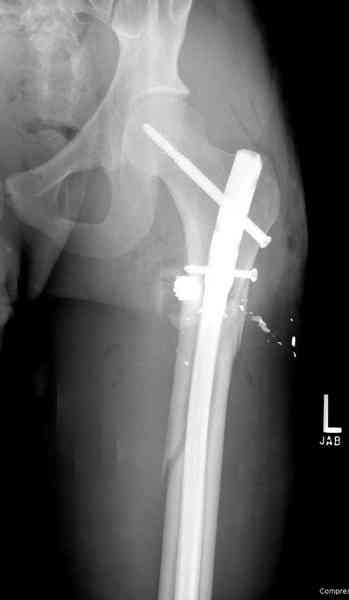

В нашем случае 21 летний боец уличного фронта, фиксацию провели на следующий день, зафиксирован интрамедуллярным штифтом. Не стали делать первичную хирургическую обработку точечной раны, зафиксирован как есть. Клинические снимки:

Конечно, наш случай не эталон, возможно, на месте вам виднее, может быть, нет необходимости ориентироваться на зарубежные ссылки, если получается лечить аппаратом Илизарова на месте, почему нет? Необходимо посмотреть собственный арсенал, чем фиксировать, и какая теория, иначе любой отличный метод можно превратить в источник остеомиелита.